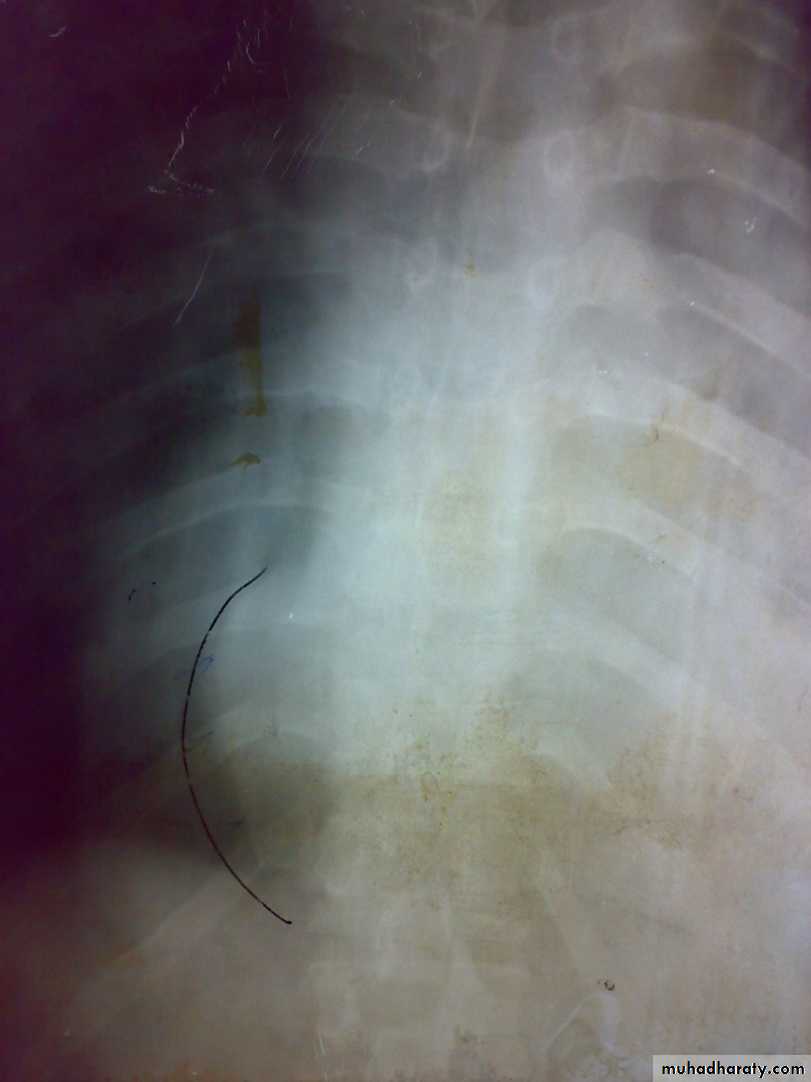

T B spondylitis may appear as localized bone erosion and collapse across an intervertebral disc space

There may be soft tissue traces of paravertebral abscess.